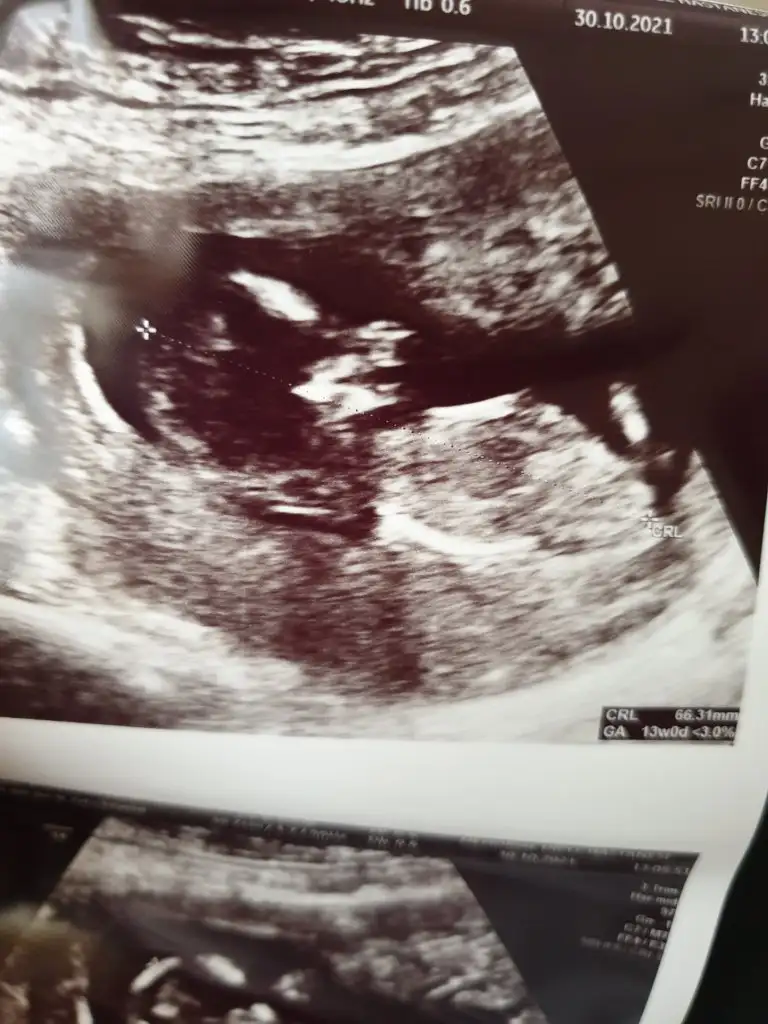

Hımm evet net değil kız mı ki acaba sizinkiSöyle bir foto var ama hic net degill

Erkek olsa gerek canım pipi orda duruyor